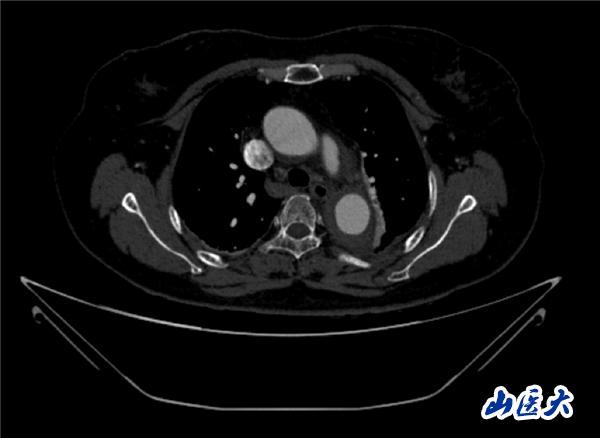

首例患者是一位55岁的女性,她患有高血压约2年时间,平时也会规律服用多种降压药,但血压控制始终不尽人意。2023年4月下午,她出现不明原因的头痛,在家拔罐缓解少许便未到医院就医,次日凌晨突感胸闷、胸背疼痛伴有呼吸困难等症状、家人急忙拨打了120,把患者送入医院急诊科进行救治,医生在急诊科行胸腹主动脉CTA时,显示主动脉弓部-降主动脉及腹主动脉壁间血肿,遂收治入医院血管外科,患者入院10天后复查血肿仍未有改善,依然伴有胸背部疼痛等不适,如不进一步处理,可能发展为夹层危及生命,患者及家属经过与医生团队了解沟通,决定进行创伤小、恢复快的介入手术治疗。张玮教授、符伟国教授、董红霖教授及其血管外科团队(闫盛、常文凯、田琴琴)共同商讨手术方案,最终确定使用Zipper™一体式主动脉弓覆膜支架系统,行胸主动脉覆膜支架腔内隔绝术+无名动脉、左颈总动脉、左锁骨下动脉分支重建术为患者进行治疗。董红霖教授及其血管外科团队根据患者术前头颅CT平扫提示双侧侧脑室旁缺血灶,血压控制不稳定,属夹层壁间血肿非典型夹层等风险点,制定了完整的手术方案,术中经股动脉置入Zipper支架主体,经预留导丝超选无名动脉,并确保主体支架对位准确,顺利置入左颈总动脉、左锁骨下动脉支架,重建弓上三分支。手术过程非常顺利。术后观察主动脉及分支覆膜支架定位准确;无内漏;分支支架通畅,动脉供血正常。

术前CTA